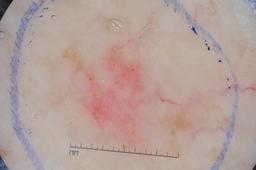

ISIC-DICM-17K (ISIC Dermoscopic Images and Clinical Metadata 17K) is a curated and balanced dataset derived from the International Skin Imaging Collaboration (ISIC) Archive Gallery. It comprises 17,060 dermoscopic images and clinical metadata (8,530 melanoma and 8,530 non-melanoma classes).

For more details, please follow the project’s GitHub repository: https://github.com/mmu-dermatology-research/isic-dicm-17k

This dataset was used in this study and benchmark to explore the effectiveness of multimodal learning for skin lesion classification:

S. Ahammed, X. Cui, W. Lu and M. H. Yap, "Skin Lesion Classification using Dermoscopic Images and Clinical Metadata: Insights from Multimodal Models," 2025 IEEE/CVF Conference on Computer Vision and Pattern Recognition Workshops (CVPRW), Nashville, TN, USA, 2025, pp. 222-230, DOI: 10.1109/CVPRW67362.2025.00027